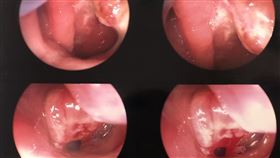

他耳朵積水被誤認中耳炎 其實已癌末

抗癌作家李歐當初就是因為中耳積水就醫,卻兩度被當成中...